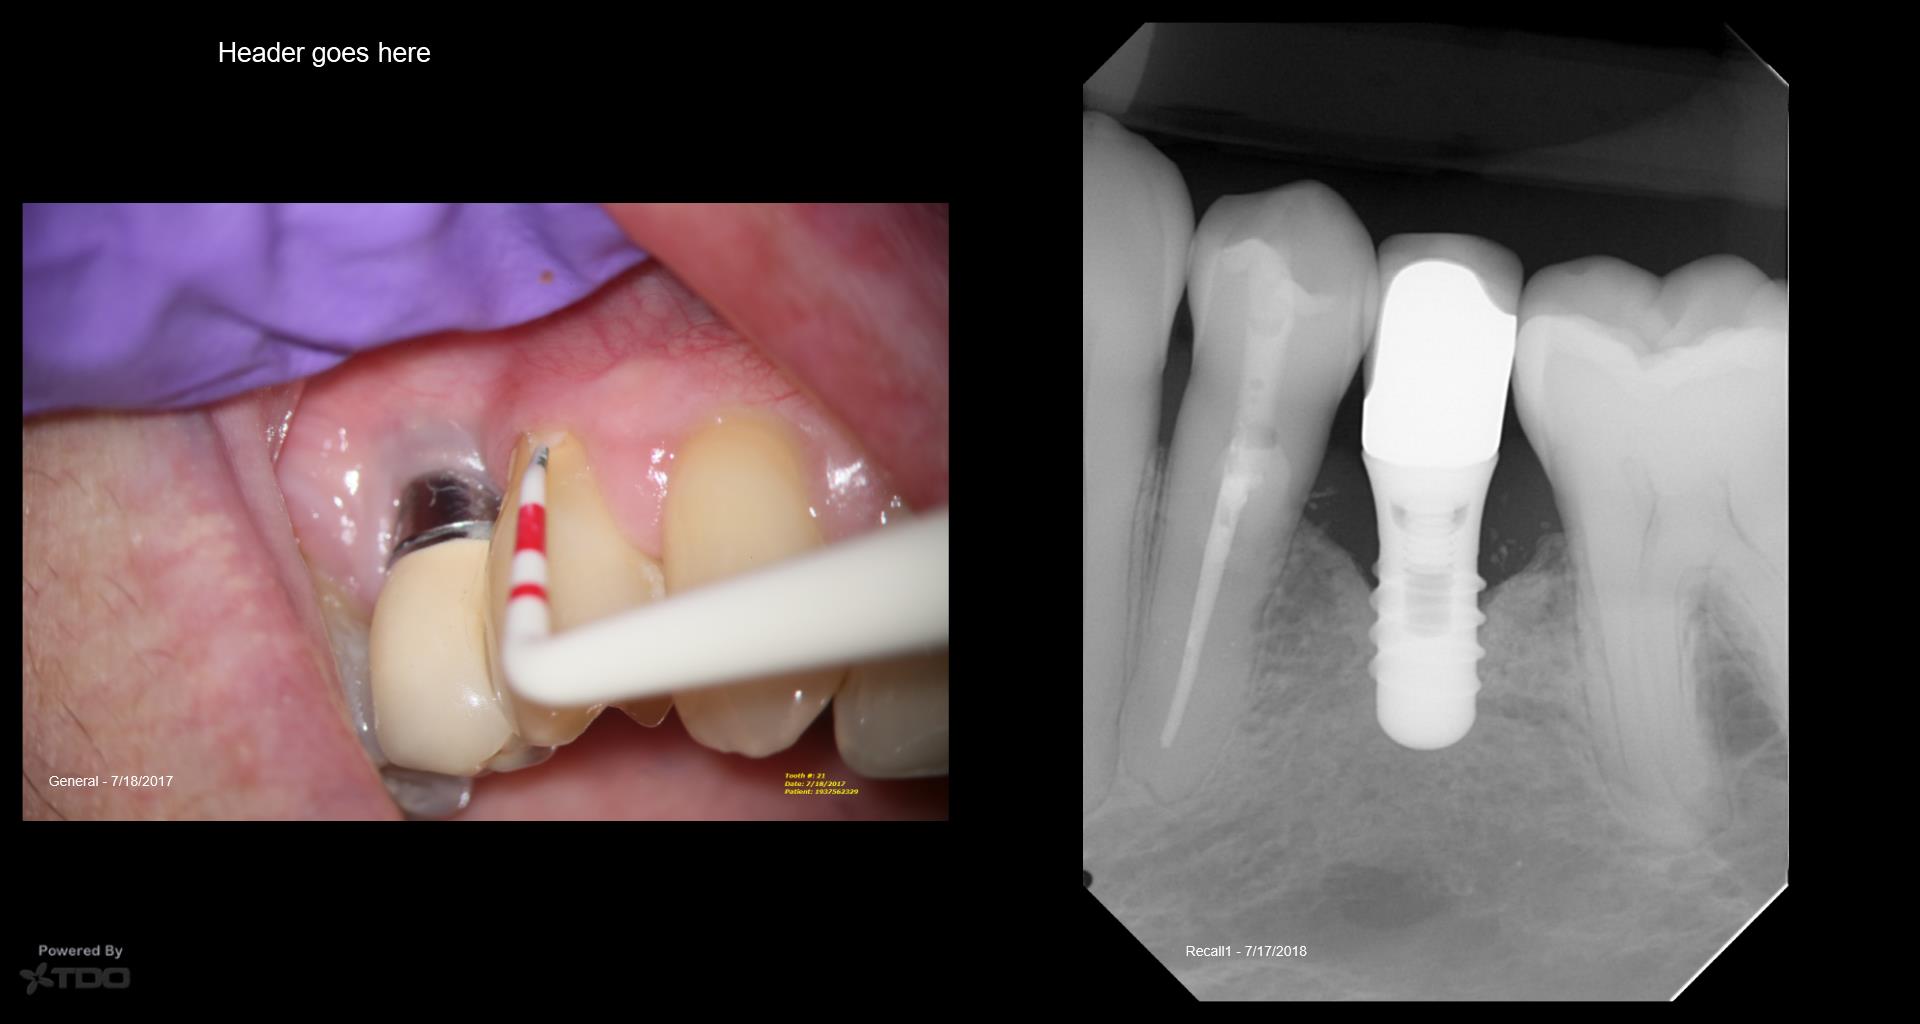

I struggled with the composite. I think I could do it better today but at least the repair seems to be holding. The defect went from line angle to line angle–the whole buccal face of the tooth. . gbc